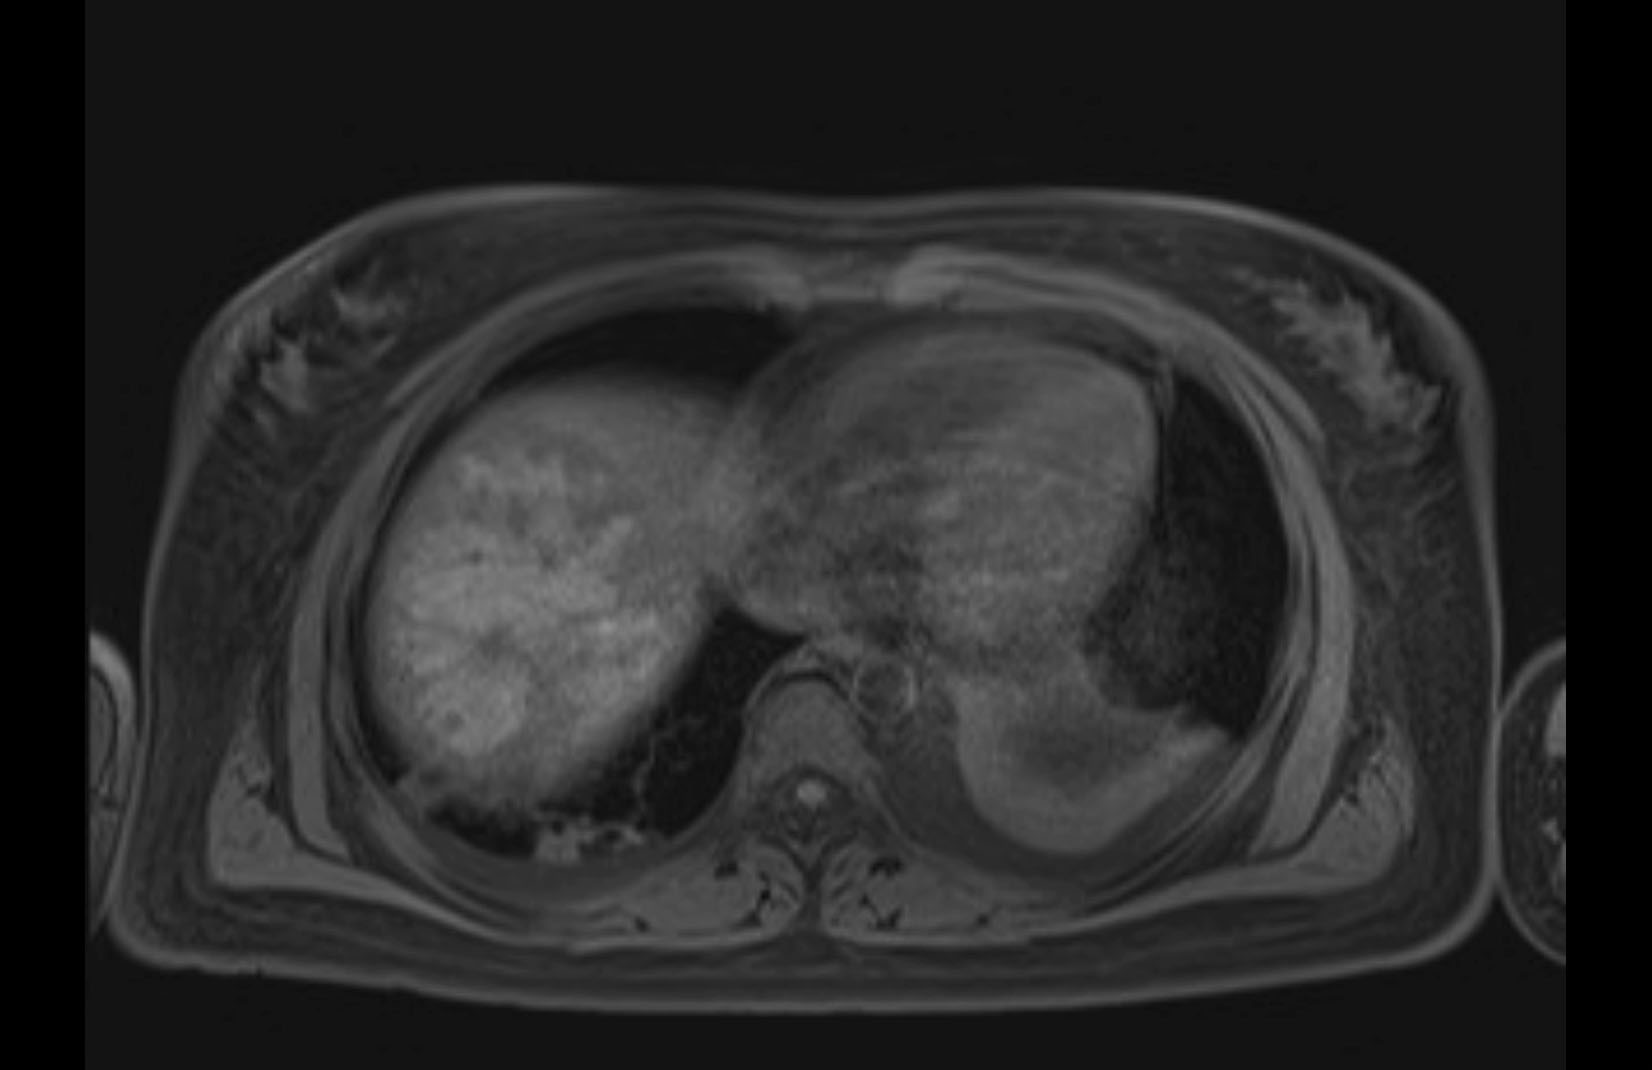

MRI T1

Imaging analysis

Based on initial findings, which issue(s) would you be most concerned about?